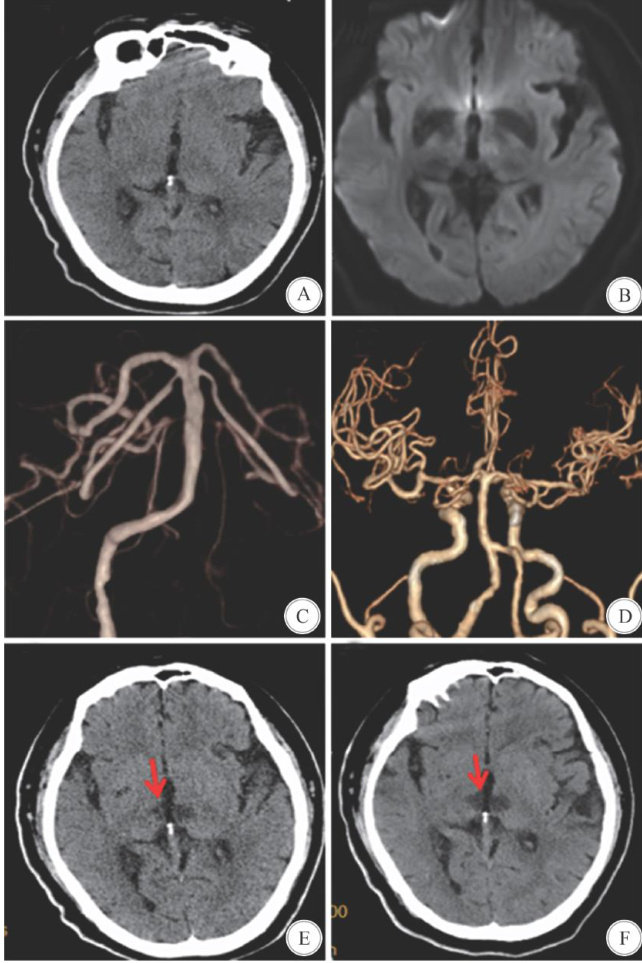

Abstract:ObjectiveTo explorethe clinical characteristics,treatment strategies and related considerations of acuteinfarctionof artery of Percheron(AoP)with negative MRIfindings.MethodsAretrospective analysis was conducted on thediagnosis and treatment processof a case of acute infarction of the AoPwith a negative MRI combined withareviewofrelevantliterature.ResultsThepatient initiallpresented withdizziness,which gradually worsened tocoma.During treatment,antiplatelet therapyand other measures to treat cerebral infarction were administered.The initial MRI DWI results were negative,and emergency angiographyand postoperative CTA did not revealany large vessel occlusion.Onthe third day post-surgery,a CTscan indicated bilateral thalamic infarction, consistentwith the diagnosis of acute infarction of the AoP.ConclusionsMRIDWI imaging inacute infarction of theAoPmayoccasionallyyield negativeresults,a phenomenon thatis exceptionallyrare.The clinical presentationof this disease is varied,and earlydiagnosis poses a significantchallnge.Afterruling out intracranial hemorhage,the possibilityof thisdisorder shouldbecontemplated,andearlyimplementationofantiplatelettherapyandotherrelevant measures are advocated.